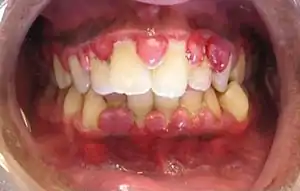

![]() | |

| A severe case of gingivitis | |

The symptoms of gingivitis are somewhat non-specific and manifest in the gum tissue as the classic signs of inflammation:

- Swollen gums

- Bright red gums

- Gums that are tender or painful to the touch

- Bleeding gums or bleeding after brushing and/or flossing

- Bad breath (halitosis)

Additionally, the stippling that normally exists in the gum tissue of some individuals will often disappear and the gums may appear shiny when the gum tissue becomes swollen and stretched over the inflamed underlying connective tissue. The accumulation may also emit an unpleasant odor. When the gingiva are swollen, the epithelial lining of the gingival crevice becomes ulcerated and the gums will bleed more easily with even gentle brushing, and especially when flossing.